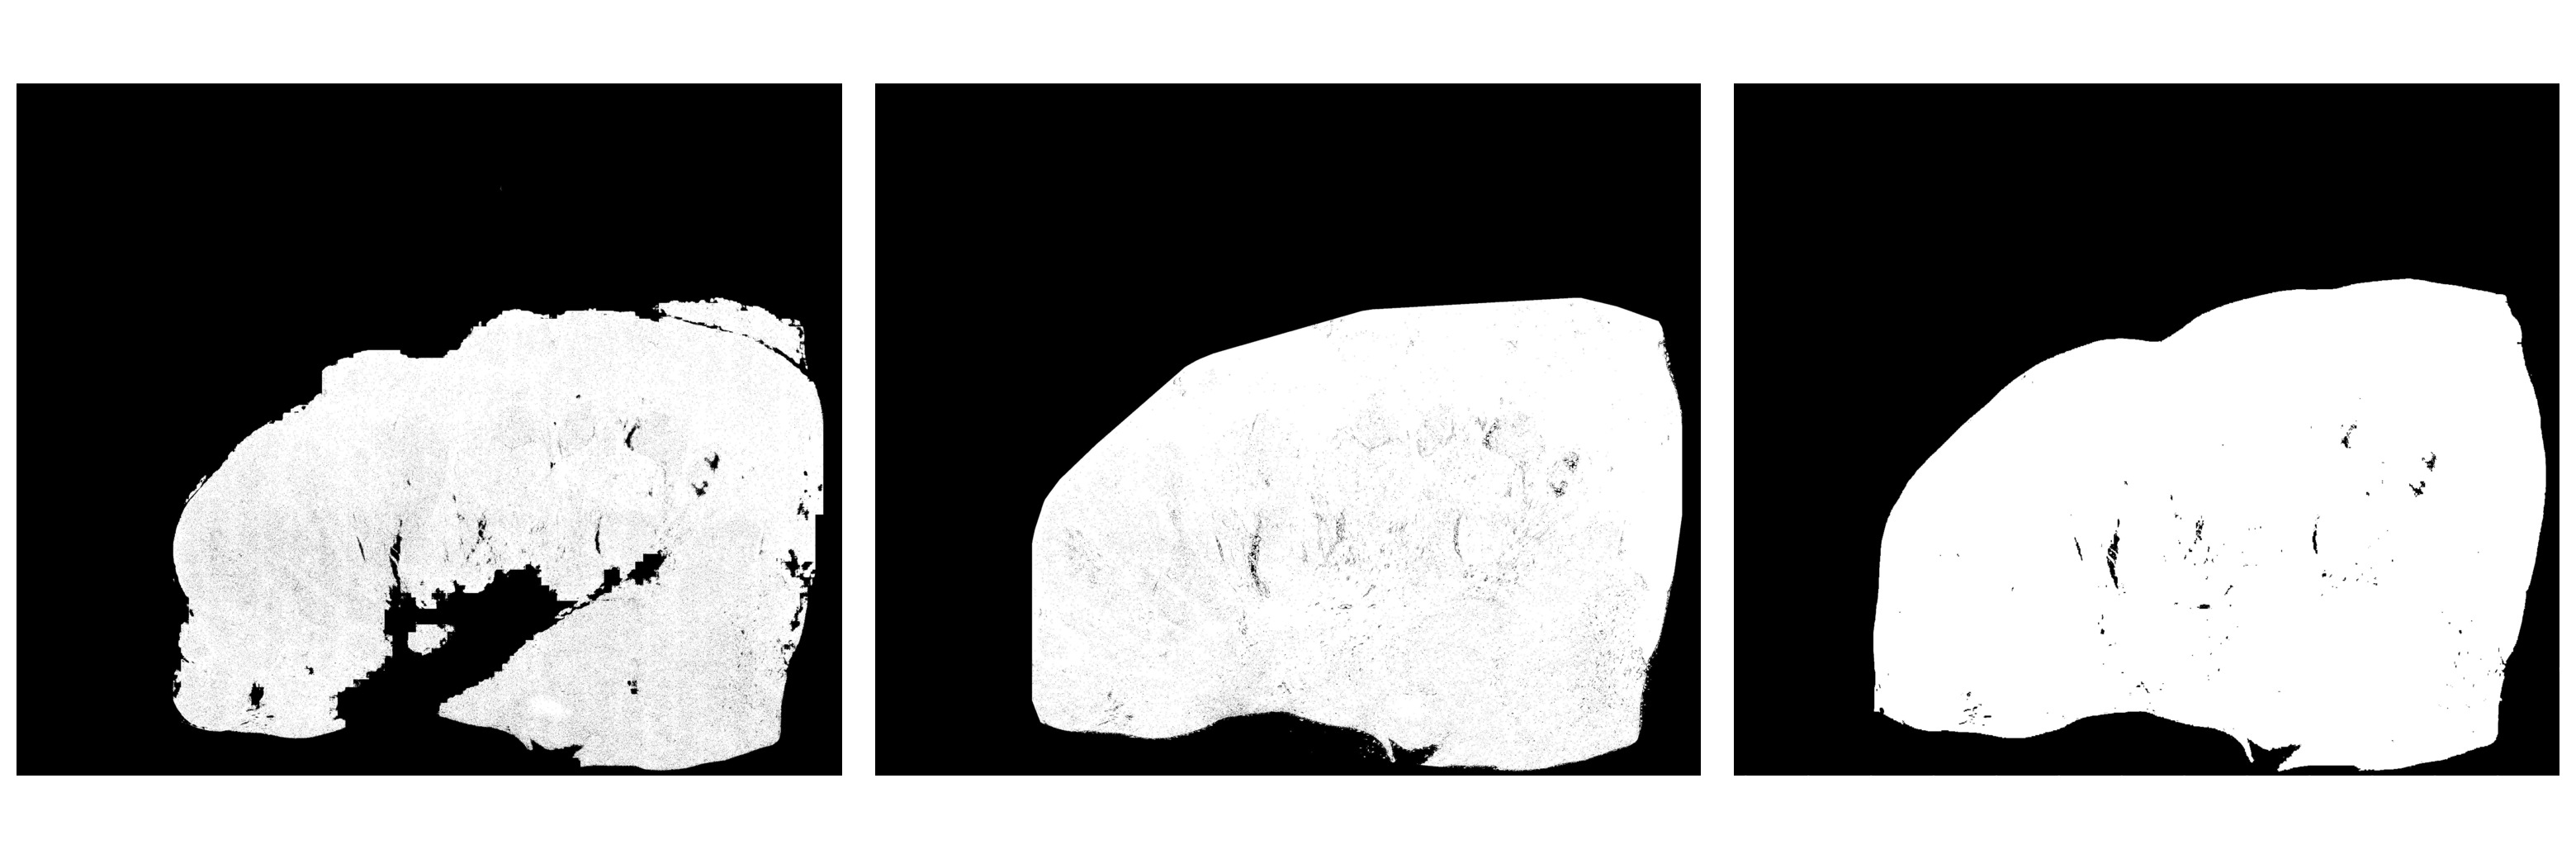

In this section, details specific to the training and inference strategies on DigestPath dataset are presented. Out of 660 tissue images from DigestPath training set, 635 images were used for training, and the remaining images were used as held-out validation set (n=25) for model selection and hyperparameter tuning. The training set (n=635) was split further into three-fold cross-validation sets; each set of data was used to train the individual models in the ensemble. A total of 80,000 patches from the entire training data were extracted, and each model was trained on patch size of 256x256 and a batch size of 32. The model inference procedure involved extraction of patches of size 256x256 with 50% overlap between adjacent patches in batches of 32. In order to generate the binary segmentation map, the predicted tumour probability map was thresholded at 0.5. Figure 11 illustrates an example of the segmentation map generated by the proposed ensemble model. The trained models were tested on held out validation set (n=25), and the corresponding results are tabulated in Table 12.